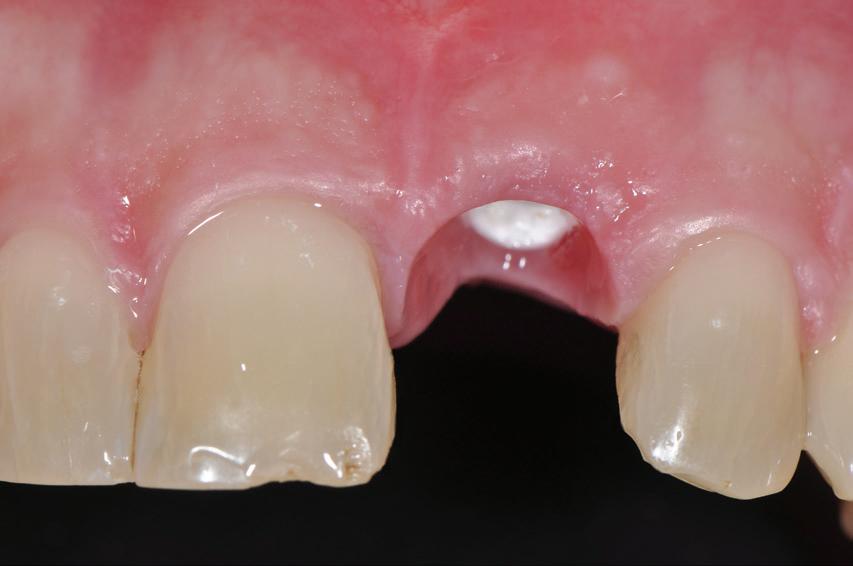

SITE AUGMENTATION Reconstituirea țesutului moale periimplantar și papilar în zona estetică

RECONSTITUIREA țesuturilor moi periimplantare. Scopul acestui raport de caz este de a demonstra procedurile chirurgicale utilizate pentru corectarea unui defect al țesuturilor moi periimplantare folosind țesutul moale interdentar în combinație cu tuberozitatea ca locație donatoare de țesut conjunctiv, utilizând o abordare prin tunelizare într-o zonă estetică.